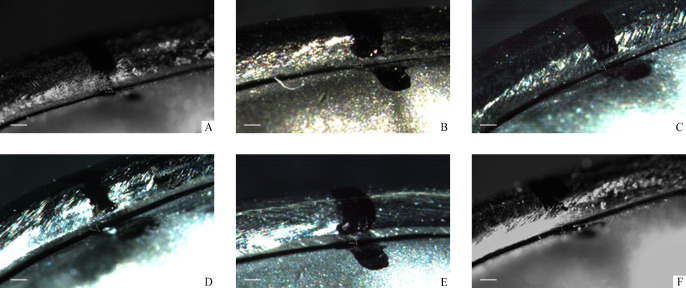

将各组卡环放置在金属基牙试件上,用体式荧光显微镜测量卡环舌侧对抗臂的起始部、中部、尖端处与基牙的间隙,取其平均值作为衡量卡环与基牙密合性的指标(图3)。

图3.

各组卡环密合度测试图(×50)

Figure 3 Test chart of clasp fitness of each group (×50)

A: Casting pure titanium group; B: Cutting pure titanium group; C: Printing pure titanium group; D: Casting cobalt chromium group; E: Cutting cobalt chromium group; F: Printing cobalt chromium group.

由于卡环唇侧的固位臂尖端处于倒凹区,不利于显微镜下测量卡环与基牙之间的间隙,而卡环舌侧对抗臂处于非倒凹区,利于显微镜下测量卡环与基牙之间的间隙,因此本研究采用荧光体式显微镜分别测量卡环舌侧对抗臂的起始部、中部、尖端处与基牙间隙,结果显示:在6个组中,打印纯钛组的卡环间隙最小,为(52.08±18.83) μm。